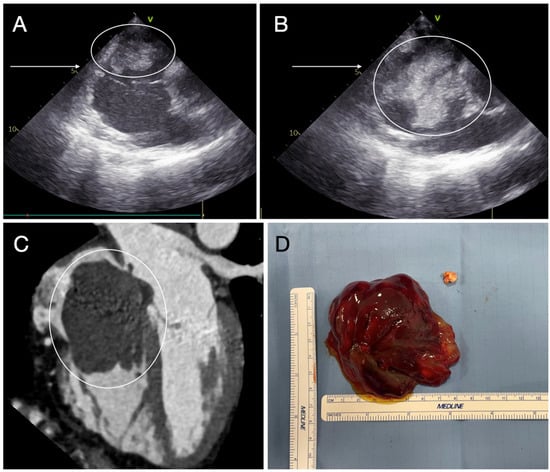

- Bianchi, G.; Margaryan, R.; Kallushi, E.; Cerillo, A.G.; Farneti, P.A.; Pucci, A.; Solinas, M. Outcomes of Video-assisted Minimally Invasive Cardiac Myxoma Resection. Heart Lung Circ. 2019, 28, 327–333. [Google Scholar] [CrossRef] [PubMed]